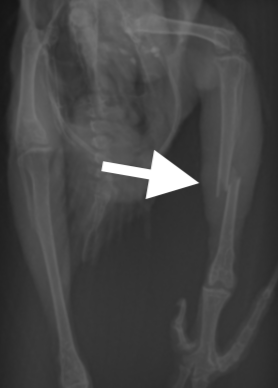

骨折部位の皮膚を最小限切開し、骨折部位を露出し、まずは遠位端(趾の方)にピンを挿入し、踵部の関節までピンを貫通させます。その後近位端にピンを挿入し、膝の関節は貫通しないように、長さを確認しながら、ピンを調節します。

最後に踵部から出ているピンを折り曲げ、適切な長さにカットし、テーピングをして手術は終了です。